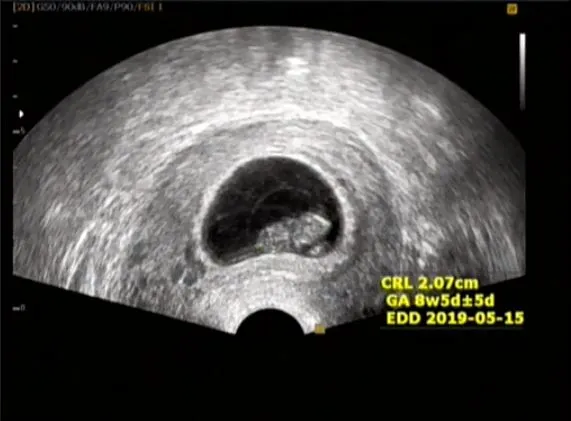

20181002_182119.jpg 짠짠이 8주 차

8주.

안정기 전까지는 매주, 어떨 때는 1주에 2번씩 병원에 가서 진료를 받고 유산방지 주사를 처방받았다. 8주가 된 짠짠이는 조금 더 형태가 생겼고 아기집도 조금 더 안정되었다. 아직 손가락만큼도 안 되는 짠짠이. 곤충처럼 머리/가슴/배 도 아니고 머리와 몸통 정도로 구분되어 보인다.